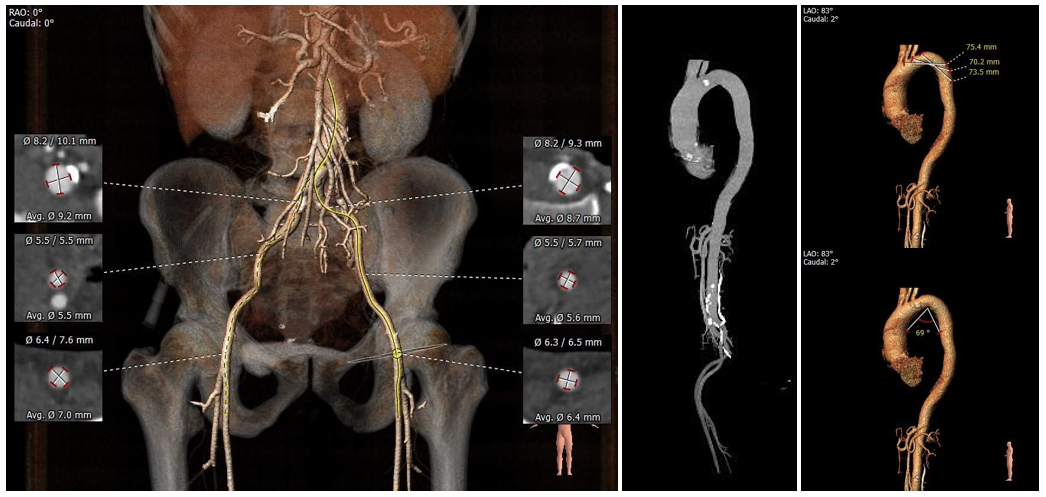

•主动脉弓、腹主动脉下段、双侧髂总动脉可见散在钙化斑块,双侧股髂动脉未见明显扭曲,股动脉穿刺处未见钙化斑块,入路血管直径尚可。

外周血管入路评估

•主动脉弓、腹主动脉下段、双侧髂总动脉可见散在钙化斑块,入路血管直径尚可,入路需规范操作,小心通过,避免入路血管相关并发症。